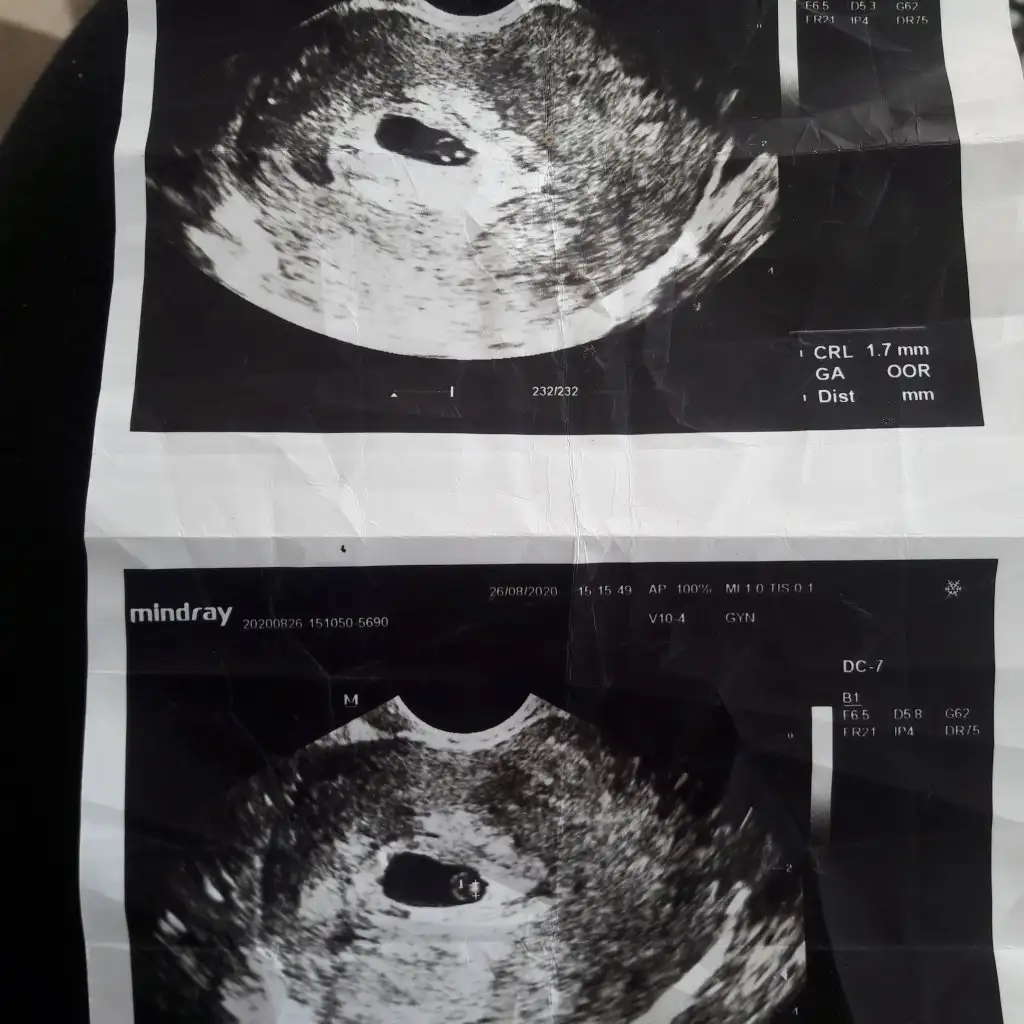

Benimkinide yorumlarmısınız 7 haftalık vajinadan bakıldı

ErkekEki Görüntüle 2699193 banada yorum yaparmısız 7 haftalik vanijina utrason